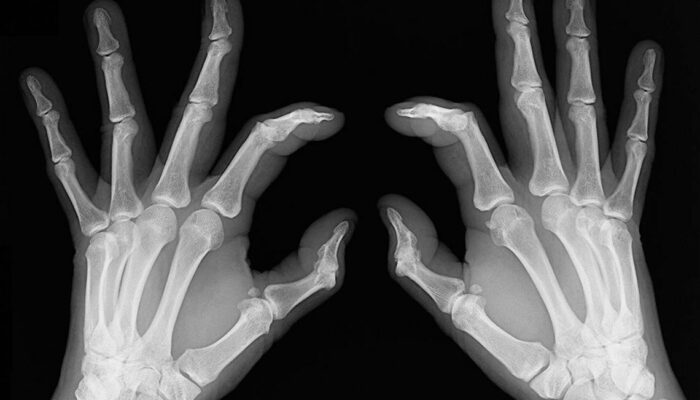

- Bone deformation: Arthritis also attacks the bones and makes them crooked and stiff. Look out for signs of any subtle changes in your joints and test them for pain levels.